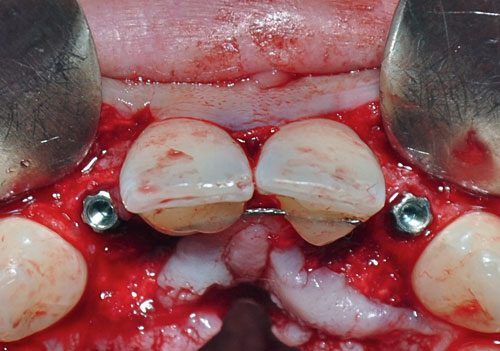

Instalamos los implantes manualmente y aplicamos dos abuttments temporarios a fin de restaurar en forma inmediata y suturamos.

Colocamos dos coronas provisionales previamente confeccionadas constituyendo un Estímulo Oclusal Inmediato. CONTROL ANUAL: CONTROL A LOS TRES AÑOS: BIBILIOGRAFÍA:

Implantes instalados

Abbutments temporarios

Tallado de los Abbutments

Dicha condición, a diferencia de la Carga Inmediata, consiste en instalar las coronas sin contacto oclusal, siendo solamente estimulado mediante la musculatura lingual y peri orbicular labial.